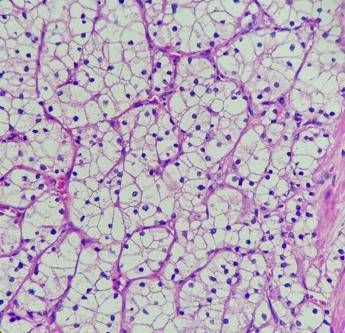

(Adnkronos) – Nei pazienti con carcinoma a cellule renali avanzato (aRcc) non precedentemente trattato, cabozantinib (inibitore della tirosin chinarsi, Tki) in associazione a nivolumab, rispetto a sunitinib, per oltre 5 anni, ha mostrato un'efficacia superiore aumentando la sopravvivenza e prolungando il tempo alla progressione del tumore, indipendentemente dalla classificazione del rischio basata sui punteggi dell'International Metastatic Renal Cell Carcinoma Database Consortium. Sono i risultati finali dello studio di fase 3 CheckMate 9ER che – informa Ipsen – saranno presentati da Robert J. Motzer durante l'American Society of Clinical Oncology Genitourinary Symposium (Asco Gu) in programma dal 13 al 15 febbraio 2025 a San Francisco, California (Abstract #439). Con un follow-up mediano di 67,6 mesi per la sopravvivenza globale (Os) – riporta una nota – lo studio ha dimostrato che i benefici iniziali di sopravvivenza della combinazione cabozantinib e nivolumab si sono mantenuti rispetto a sunitinib, con un incremento assoluto mediano dell'Os di 11,0 mesi (46,5 mesi per la combinazione vs 35,5 mesi per sunitinib, rapporto di rischio (Hr) 0,79, intervallo di confidenza (Ci) 95%: 0,65-0,96. Inoltre, la combinazione ha dimostrato una riduzione del 42% del rischio di progressione di malattia o di morte, con una sopravvivenza libera da progressione mediana raddoppiata per la combinazione rispetto a sunitinib, 16,4 vs 8,3 mesi rispettivamente (Hr 0,58; 95% Ci: 0,49-0,70). Il profilo di sicurezza è risultato in linea con quelli già noti dei singoli farmaci, con eventi avversi correlati al trattamento che si sono verificati nel 98% dei pazienti trattati con la combinazione rispetto al 93% di quelli trattati con sunitinib. Non sono emerse nuove segnalazioni di sicurezza. "Nell'ultimo anno sono state stimate oltre 13mila nuove diagnosi di carcinoma renale in Italia, un numero ancora molto elevato e che sottolinea la necessità di trovare opzioni terapeutiche sempre più innovative, in grado di cambiare il corso di questa neoplasia – afferma Chiara Marchesi, Medical & Regulatory Affairs Director Ipsen Italia – I risultati dello studio CheckMate 9ER hanno contribuito in modo significativo alla trasformazione del panorama terapeutico del carcinoma a cellule renali negli ultimi anni. La combinazione di cabozantinib e nivolumab sta dimostrando significativi benefici a lungo termine per più di cinque anni, confermandosi così un trattamento standard che permette ai pazienti una maggiore sopravvivenza". Nel 2022 sono stati diagnosticati più di 400mila nuovi casi di tumore del rene a livello globale. Tra questi, il carcinoma a cellule renali (Rcc) è il tipo più comune di tumore del rene (circa il 90% dei casi). E' quasi 2 volte più comune negli uomini e i decessi dei pazienti maschi rappresentano oltre i due terzi. L'Rcc in stadio iniziale spesso non presenta sintomi distintivi, il che porta il 30% delle persone a ricevere la diagnosi in una fase avanzata di malattia. Tra i pazienti con Rcc avanzato, il 60% non riceve un trattamento di seconda linea. Se diagnosticato in stadi iniziali, il tasso di sopravvivenza a 5 anni è elevato, ma nei pazienti con Rcc metastatico in stadio avanzato il tasso di sopravvivenza è decisamente più basso, intorno al 17%. "Il 60% dei pazienti con carcinoma a cellule renali avanzato – sottolinea Camillo Porta, oncologo medico e professore all'Università di Bari 'A. Moro' – non arriva alla terapia di seconda linea: questo dato sottolinea l'importanza di assicurare le cure più efficaci il prima possibile. Il fatto di poter contare su un'unica chance di trattamento per così tanti pazienti rende i risultati finali di CheckMate 9ER davvero rilevanti per la pratica clinica quotidiana. Infatti, questi dati finali convalidano ulteriormente la possibilità di ottenere una sopravvivenza a lungo termine con cabozantinib e nivolumab a questo stato avanzato della malattia". —salutewebinfo@adnkronos.com (Web Info)